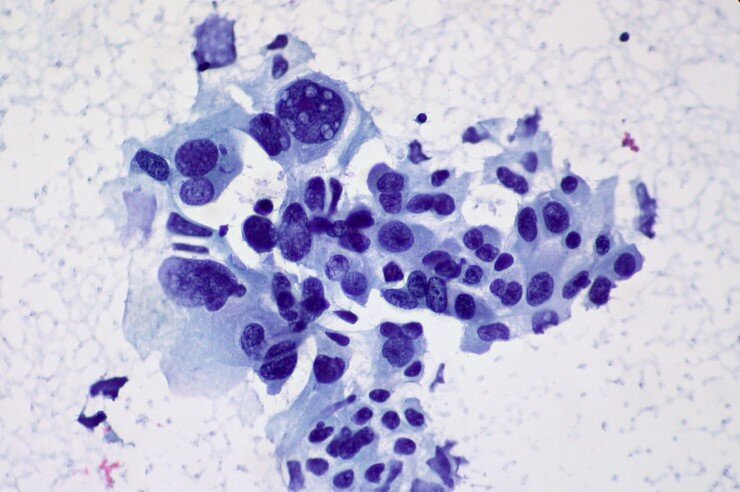

Немелкоклеточный рак легкого. © CC BY 2.0/Ed Uthman